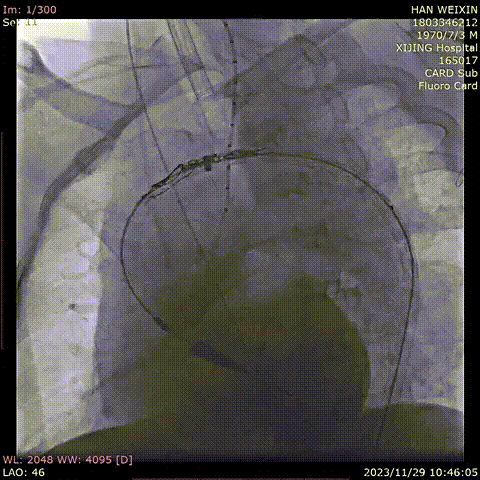

韩某,男,53岁,“查体发现主动脉弓部溃疡15天”入院,主动脉CTA提示:主动脉溃疡(弓部);2. 主动脉壁内血肿。患者高血压病史8年,最高210/130mmHg,无规律服药。

术前 CTA

术前造影

导入弓部

主体支架

释放弓部

超选左颈总动脉

超选无名动脉

并预置导丝

导入左颈总

支架并释放

导入无名动脉

超选左锁骨下

动脉

导入左锁骨下动脉

导入并释放远端支架

术前

术后

手术用时115分钟